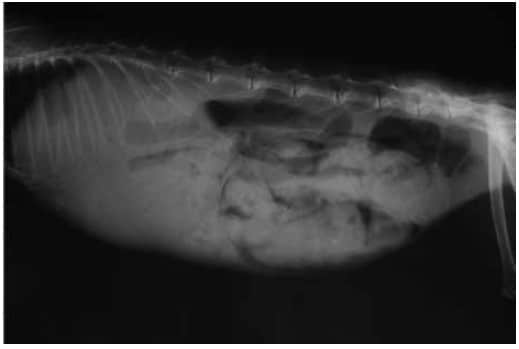

体温:36.7℃、呼吸:70次/min、心跳:150次/minX光片检查:

图一:侧位片(可见肠道内积大量粪便及气体,胃内有大量食糜)